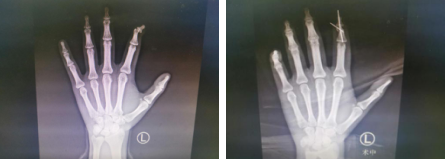

术前

5月27日下午,李甲主任手术团队为小枫进行了“左手指瘢痕松解+截骨矫形固定+筋膜皮瓣修复术”。术中,手术团队将小枫左手示指肌腱与指骨分离,暴露指骨,从中节指骨头端做一楔形截骨。见桡侧瘢痕粘连严重,倾斜角度差,从切口内锐性分离松解桡侧瘢痕组织。予以2枚克氏针内固定,远节指骨与近中节指骨总体呈同一总轴线。手术顺利,全程不到2小时。

术前(左图)术后即刻(右图)